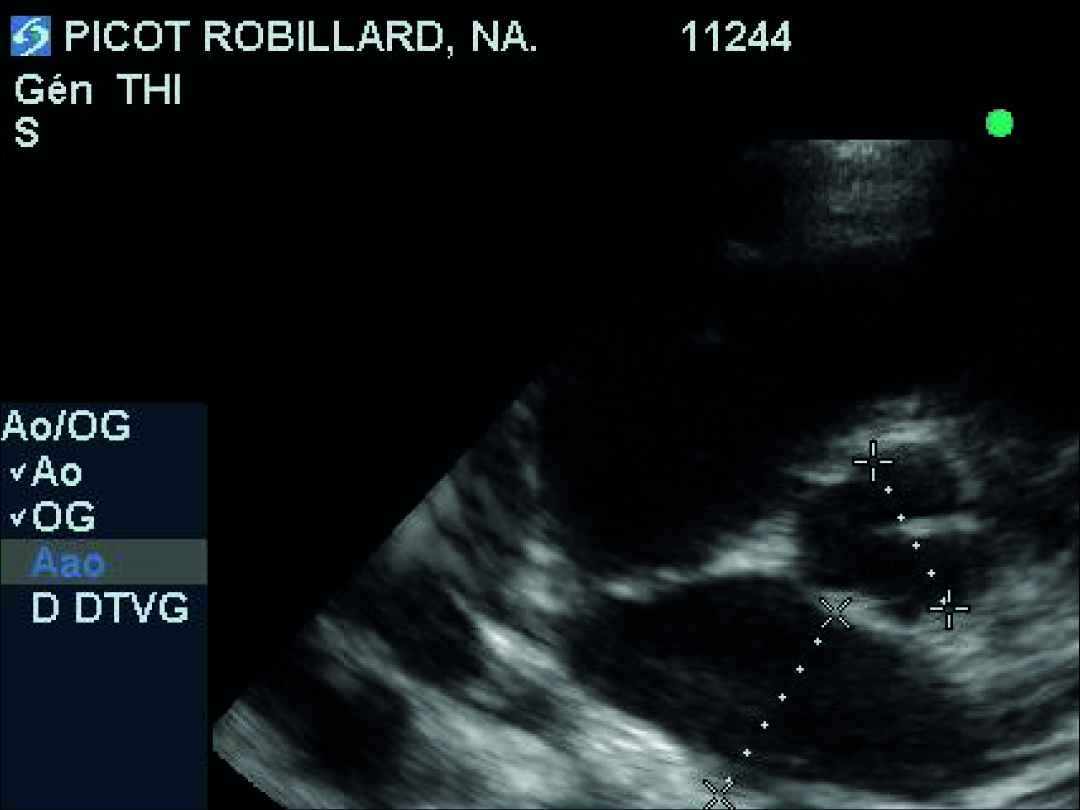

- L'examen échocardiographique révèle une insuffisance de la valve mitrale centrale, peu évoluée, sans aucun remodelage des feuillets mitraux, ni modifications des dimensions de l'atrium gauche et du ventricule gauche (VG normalisé à 1,7 : discrètement au-dessus de la norme) : stade ACVIM B1. La distance point E-Septum est estimée à 10 mm (norme supérieure acceptée : 7 mm). On note donc essentiellement une mauvaise fermeture des feuillets mitraux par agrandissement de l'anneau mitral. Enfin, une petite fuite pulmonaire est visualisée mais sans aucune répercussion sur l'état clinique ou hémodynamique du coeur (cavités droites sans aucun signe de souffrance).

Un suivi clinique et échocardiographique (tableau n° 2, photos n° 1, 2 et 3), électrocardiographique (photo n° 4) et mesure du NT-proBNP (tableau n° 3) sont entrepris sur 12 mois avec une visite à 4 mois (V2), 6 mois (V3) et 12 mois (V4).

Au cours des examens échocardiographiques, une très faible dilatation de l'atrium gauche a été observée (passage d'un rapport OG/Ao de 1 à 1,4). La dilatation du VG ne s'est pas aggravée au cours des 12 mois (42 mm en télédiastole à V1 et V4). On note une amélioration puis une stabilisation de la distance point E-Septum.